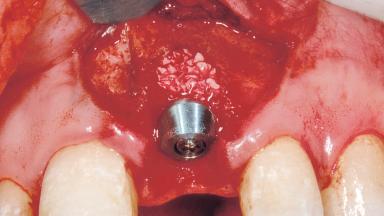

A 33-year-old female patient presented with an upper left central incisor that required extraction after a failed endodontic therapy. The tooth had been traumatized when the patient was a teenager and had undergone several endodontic treatments, including two apicectomy procedures. The patient was in good health and did not smoke. Clinical examination showed that the patient had a high lip line. In full smile, the gingival margins of the upper teeth were visible to the first molars. The gingival margins of central incisors 11 and 21 were only just showing. Examination of tooth 21 confirmed that the tooth was mobile and had hypererupted by 1 mm.

Placement Protocol Immediate implant placement

Socket Morphology Single-root socket

Socket Integrity Damage to one or more bone walls

Bone Volume Damage to one or more socket walls